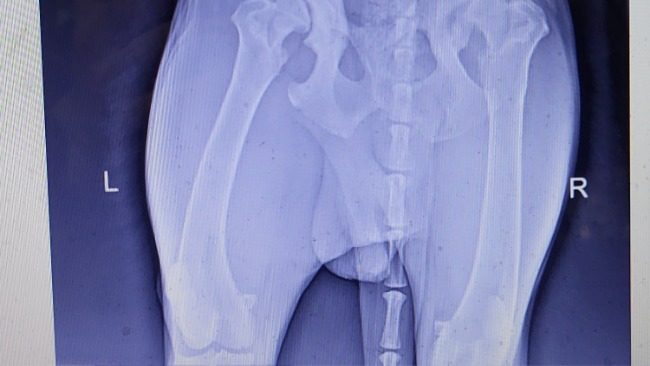

Niestety sprawdzenie hodowli i dokumentów nie wystarczyło 💔💔💔, ponieważ okazało się, że ma wadę genetyczną jaką jest dysplazja. Po konsultacji weterynaryjnej oraz zdjęciu RTG, okazało się, że Ares ma obustronną dysplazje😔. Choroba jest zaawansowana - po konsultacji z weterynarzem otrzymaliśmy informację, że Ares może przestać chodzić po ok 5 lub 6 roku życia 😥😭. Dlatego konieczne są 2 operacje (lewego i prawego biodra).